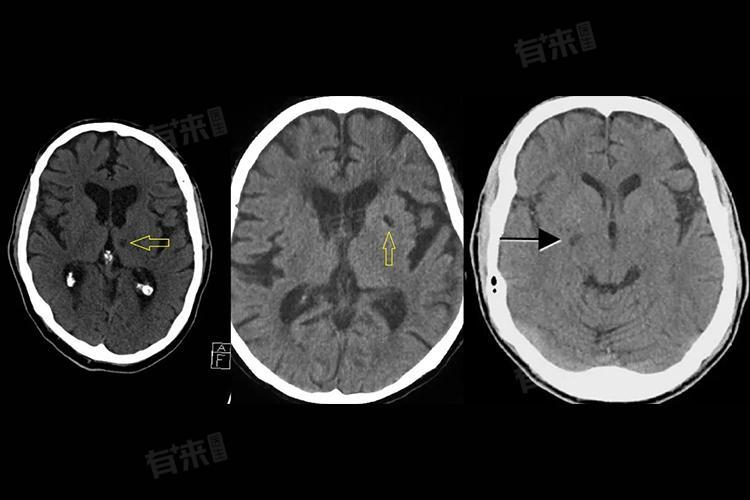

它通常发生在脑内非常细小的穿支动脉,比如:

基底节区丘脑内囊脑桥

这些血管直径非常小,一旦堵塞,形成的梗死区域往往只有几毫米到1厘米左右,医学上称为“腔隙”。

简单理解就是:脑内的小血管堵了一下,留下一个很小的“疤痕”。